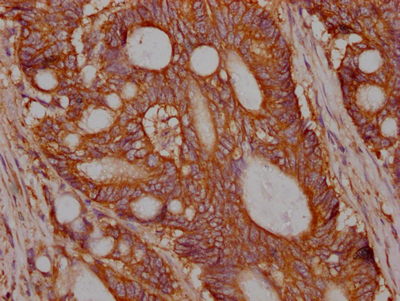

IHC image of CSB-RA983271A0HU diluted at 1:100 and staining in paraffin-embedded human colon cancer performed on a Leica BondTM system. After dewaxing and hydration, antigen retrieval was mediated by high pressure in a citrate buffer (pH 6.0). Section was blocked with 10% normal goat serum 30min at RT. Then primary antibody (1% BSA) was incubated at 4℃ overnight. The primary is detected by a Goat anti-rabbit IgG polymer labeled by HRP and visualized using 0.05% DAB.